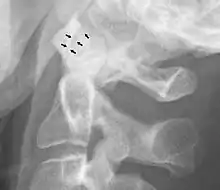

Normal atlanto-dental joint on projectional radiography.

A widening of the atlanto-axial joint, as measured between the posterior surface of the anterior arch of atlas and the front of the odontoid process, indicates an injury to the transverse atlantal ligament.[5] Normally, this atlanto-dental distance is less than 2 mm, sometimes a maximum of 3 mm is accepted in men and 2.5 mm in women.[5]